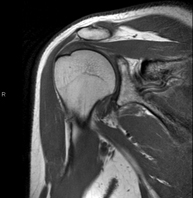

- RM d'Espatlla

Exploració per a l'estudi de lesions en els tendons, els músculs i les articulacions. La seva principal utilitat resideix en diagnosticar les lesions dels tendons del braçal rotatori. Té una durada aproximada de 20 minuts. No utilitza radiació ionitzant. - RM de Braç

Exploración para el estudio de las lesiones en pequeñas estructuras anatómicas de la articulación que suelen lesionarse en pacientes que sufren luxación o inestabilidad crónica. El estudio viene precedido por una inyección de contraste en el interior de la articulación, realizada bajo control de rayos X. La duración global de los dos procedimientos es de 50 minutos. - Artro-RM Muñeca